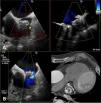

Via right femoral venous access and guided by TEE, transseptal puncture and introduction of a deflectable sheath Agilis 8.5 F Medium Curl (Abbott, IL, USA) in the left atrium were performed. A multipurpose guiding catheter 5F and straight hydrophilic guide (Terumo Europe, Leuven, BE) were introduced through it. Both defects were crossed sequentially and two 12 mm Amplatzer Vascular Plug II (Abbott, IL, USA) devices were released (Figures 2 and 3A and Video 3-6).

A: Fluoroscopy imaging showing how the guide catheter crossed the upper leak. B: Angiographic image showing the deployment of the first Amplatzer Vascular Plug II into the upper leak. C: Angiographic image showing how the guide catheter crossed the lower leak. D: Fluoroscopy image showing the release of the second Amplatzer Vascular Plug II into the lower leak.

The procedure was performed without complications, and the patient was discharged the following day with aspirin and clopidogrel. The four-week follow-up TEE showed the devices had been implanted appropriately implanted (Figure 3B).